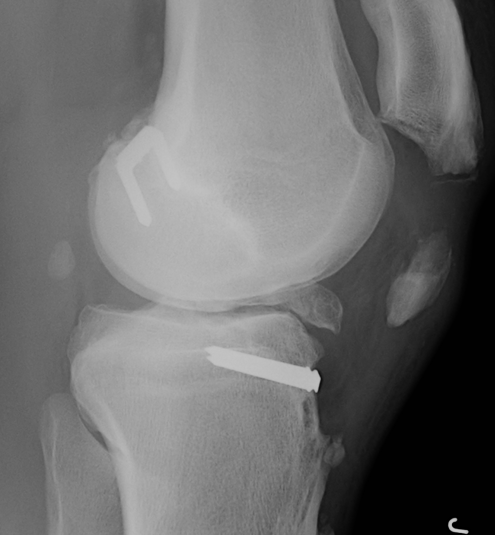

2. Extra-Articular Augmentation

Lateral extra-articular procedures

- prevent anterior subluxation LFC in extension

- unpopular due to poor long term results

1. Ellison Procedure

A. Strip of ITB Deep to LCL

- placing it anterior in a bone trough

B. Plication the capsular ligament

2. MacIntosh Procedure

ITB left attached distally

- deep to LCL

- subperiosteal tunnel in LFC

- thru intermuscular septum

- back on itself distally